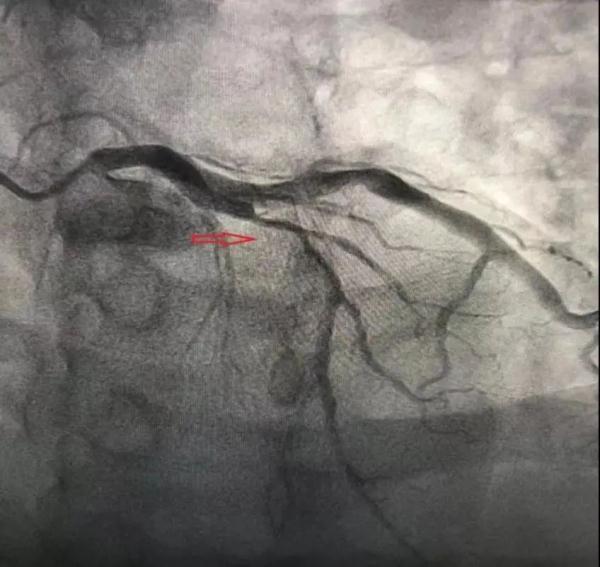

最新 血管造影糖尿病(糖尿病足的血管造影) 文章目录:1、长沙32岁男子患冠心病,血管堵塞近80%!医生紧急提醒2、糖尿病患... 光明网 2025-01-13 39 # 冠心病 # 高血压 # 心肌梗死 # 长沙 # 心血管 # 糖尿病 # 睡现在你最想逃离什么 # 心脏病 # 体检 # 世界卫生组织 # 高血脂 # 酒 # 长沙晚报 # 王勇